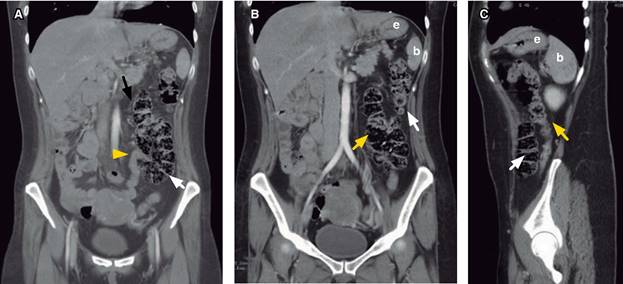

Figura 1: Imágenes de tomografía computarizada con doble contraste de abdomen mostrando en corte coronal (A) a la válvula iliocecal en cuadrante inferior izquierdo (cabeza de flecha amarilla) y ciego (flecha blanca); en corte coronal (B) y en corte sagital (C) al colon descendente (flecha amarilla) y al colon ascendente (flecha blanca).